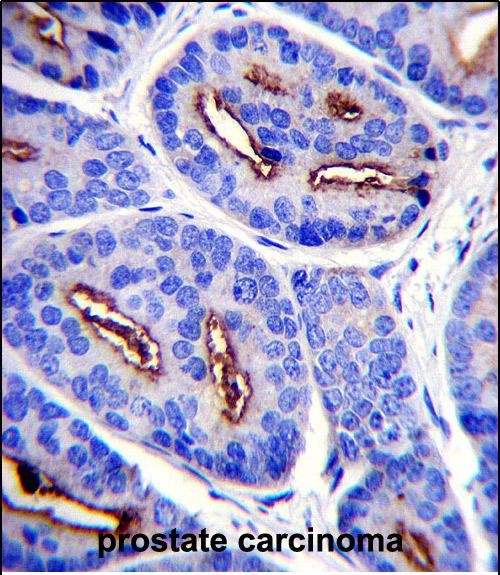

IHC 1/100-1/500 Human,Mouse,Rat

The FOLH1 (N-term) antibody targets the N-terminal region of folate hydrolase 1 (FOLH1), also known as prostate-specific membrane antigen (PSMA) or glutamate carboxypeptidase II (GCPII). FOLH1 is a type II transmembrane glycoprotein with enzymatic activity, primarily cleaving terminal glutamate residues from substrates like N-acetylaspartylglutamate (NAAG) and poly-γ-glutamated folate. It plays roles in nutrient absorption, folate metabolism, and neuropeptide regulation.

FOLH1 is highly expressed in prostate cancer cells and is a well-established biomarker for prostate cancer diagnosis, prognosis, and therapeutic targeting. It is also found in tumor neovasculature of various cancers (e.g., renal, colorectal), making it a candidate for antibody-based imaging or therapy. The N-terminal region is extracellular, enabling antibodies against this domain to bind cell-surface FOLH1. facilitating applications in immunohistochemistry (IHC), flow cytometry, or functional studies.

The FOLH1 (N-term) antibody is widely used in research to investigate FOLH1’s biological roles, tumor expression patterns, and therapeutic potential. Its specificity for the N-terminus ensures recognition of full-length, membrane-bound FOLH1. avoiding cross-reactivity with truncated isoforms. This antibody supports advancements in developing PSMA-targeted therapies, including antibody-drug conjugates, radioligands, and CAR-T cell platforms, underscoring its importance in oncology and molecular biology research.